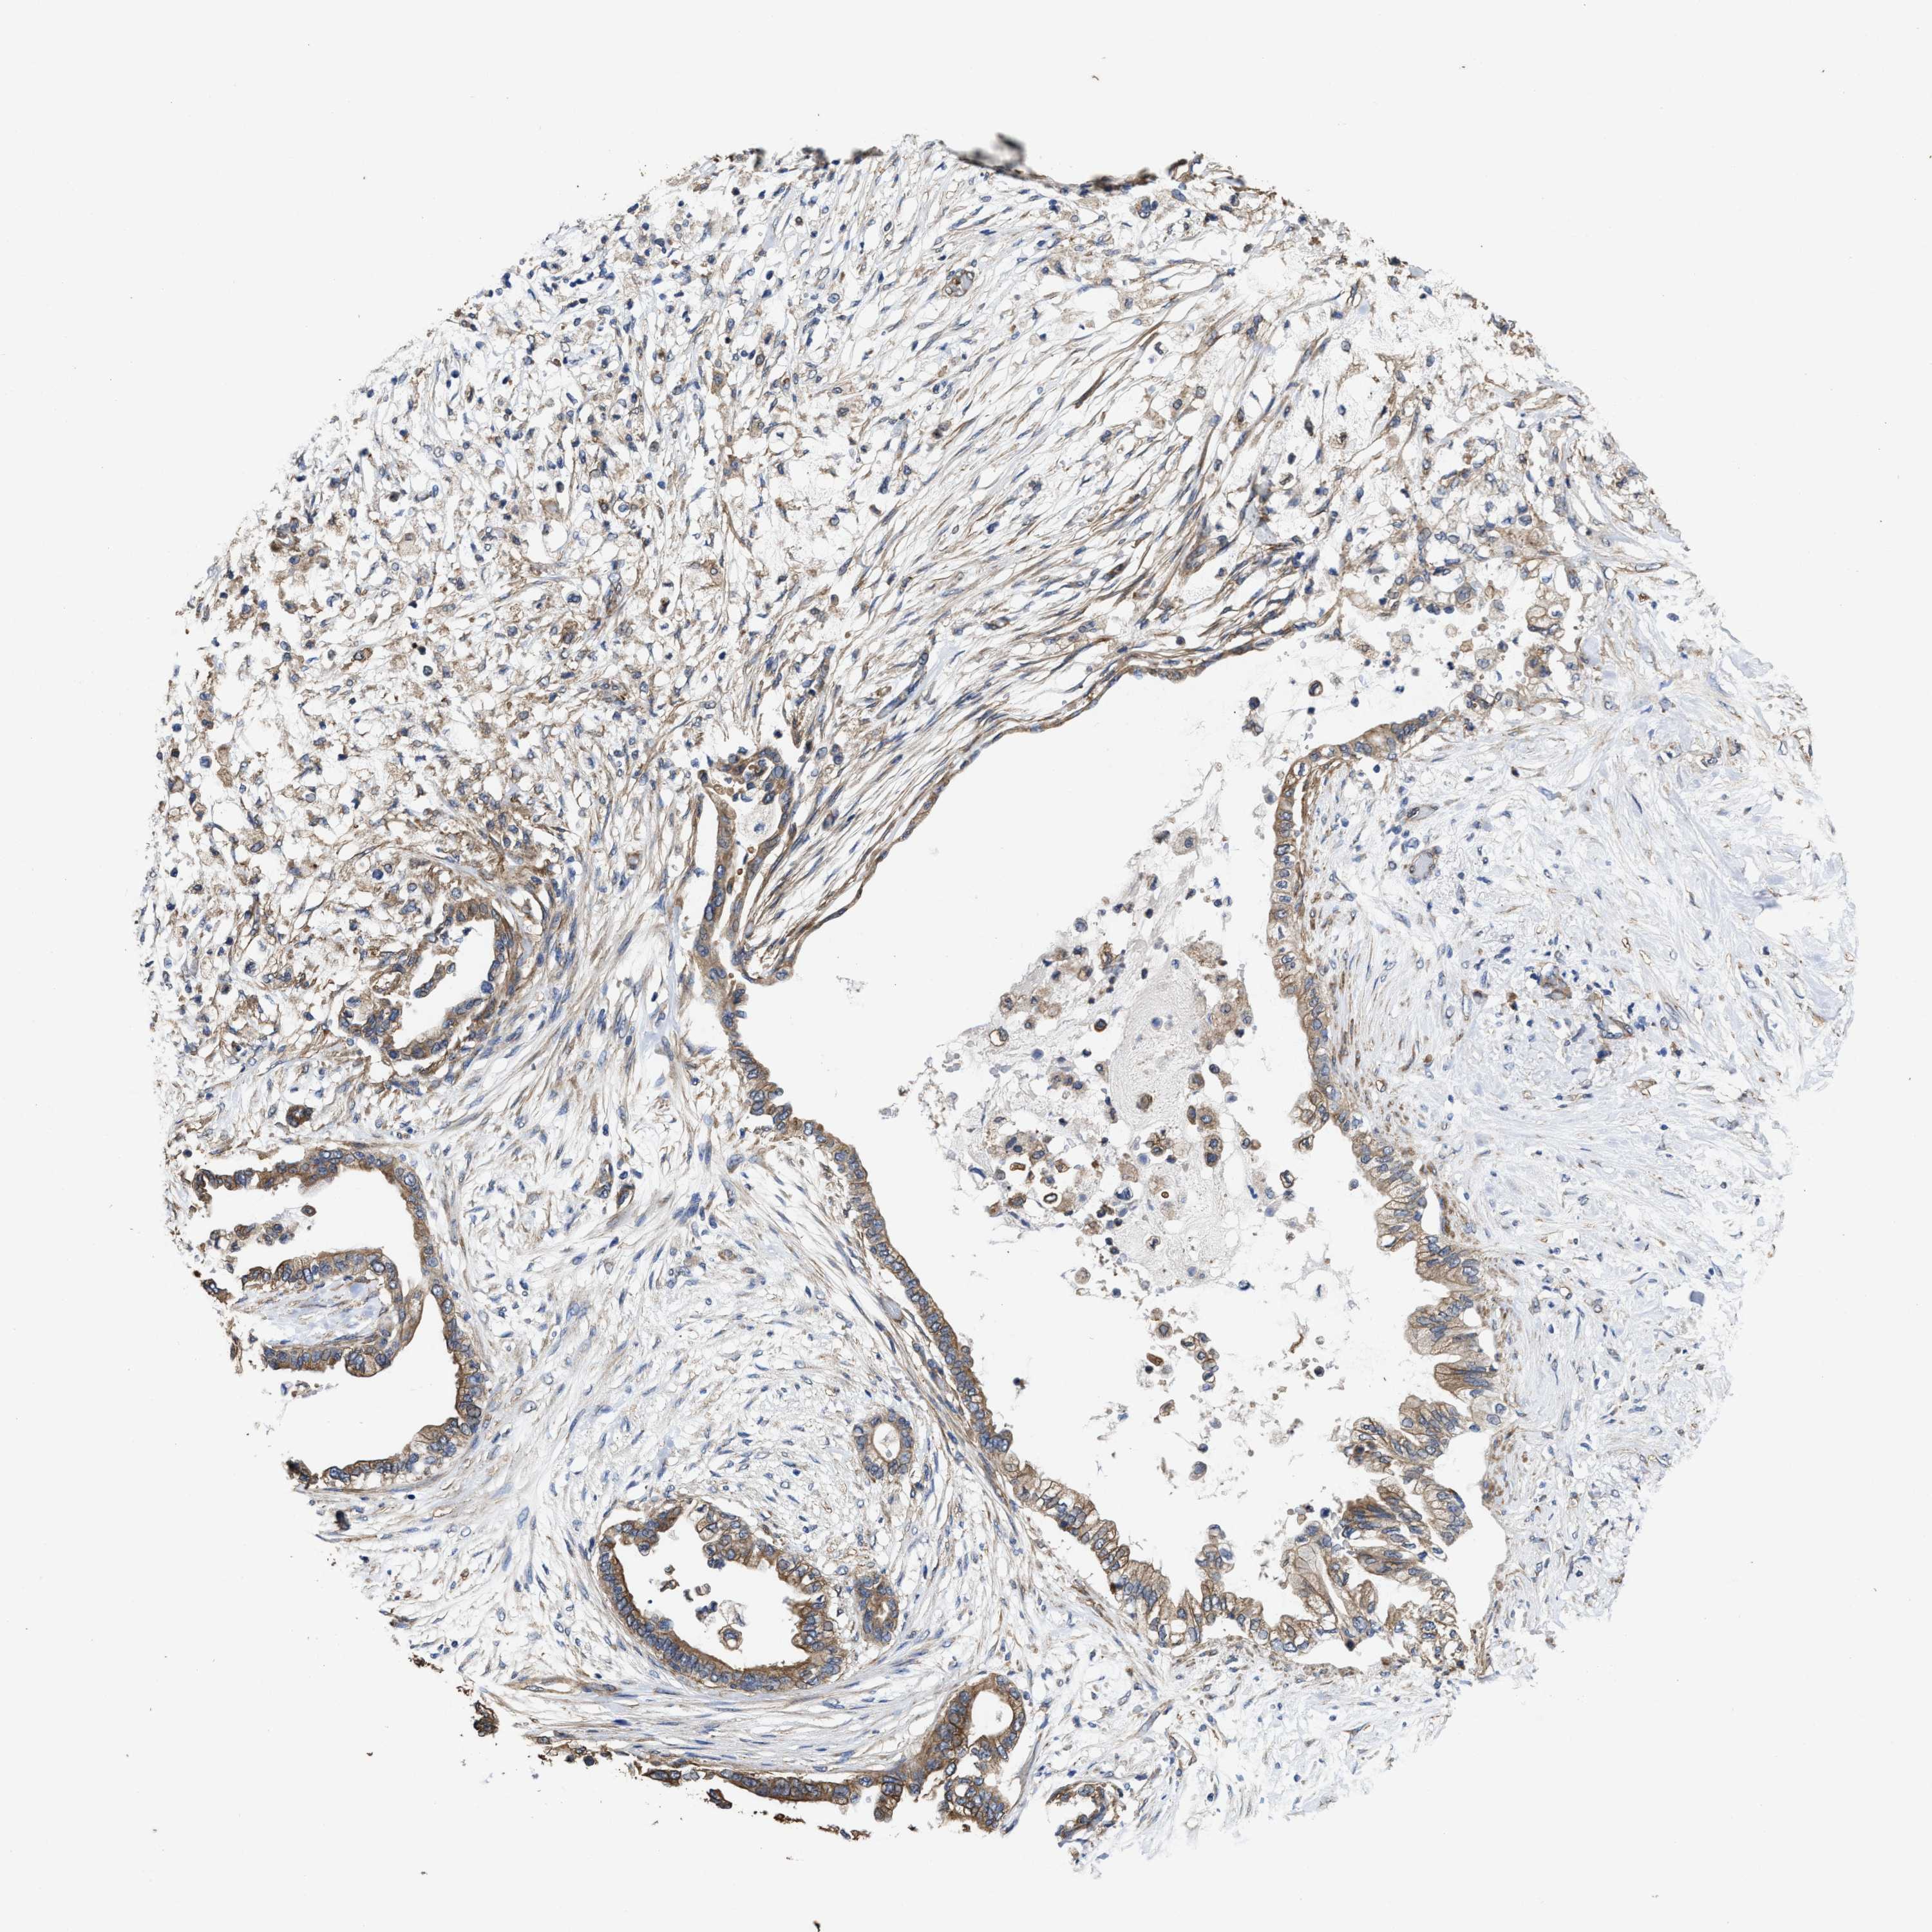

PANCREATIC CANCER - Protein expressioni

A mouse-over function shows sample information and annotation data. Click on an image to view it in a full screen mode. Samples can be filtered based on level of antibody staining by selecting one or several of the following categories: high, medium, low and not detected. The assay and annotation is described here.

Note that samples used for immunohistochemistry by the Human Protein Atlas do not correspond to samples in the TCGA dataset.

Antibody stainingi

Antibody staining in the annotated cell types in the current human tissue is reported as not detected, low, medium, or high, based on conventional immunohistochemistry profiling in selected tissues. This score is based on the combination of the staining intensity and fraction of stained cells.

Each image is clickable and will lead to virtual microscopy that enables deeper exploration of all samples and also displays staining intensity scores, fraction scores and subcellular localization as well as patient and tissue information for each sample.

Antibody HPA020872

Staining

High

Medium

Low

Not detected

Intensity

Strong

Moderate

Weak

Negative

Quantity

>75%

75%-25%

<25%

None

Location

Nuclear

Cytoplasmic/membranous

Cytoplasmic/membranous,nuclear

Adenocarcinoma, NOS